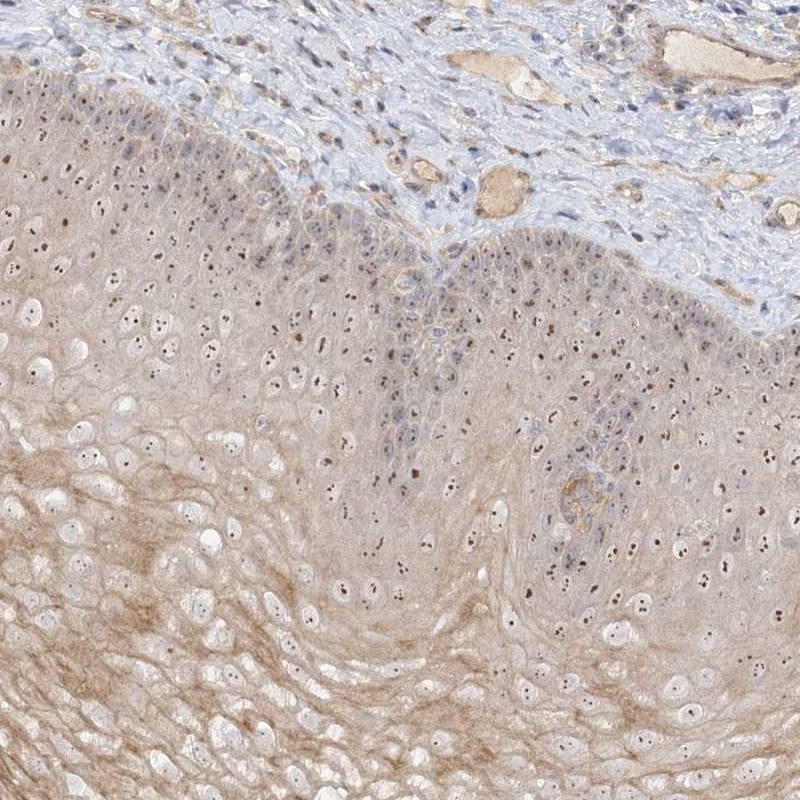

Immunohistochemical staining of human esophagus shows distinct nucleolar positivity in squamous epithelial cells.